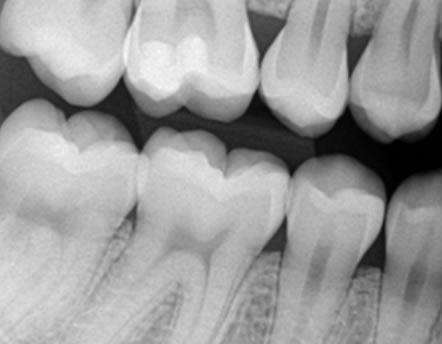

Bitewing snimka zubi - To je snimka stražnjih gornjih i donjih zuba, koristi se za detekciju početnog karijesa između stražnjih zubi.

Bitewing snimka zubi - To je snimka stražnjih gornjih i donjih zuba, koristi se za detekciju početnog karijesa između stražnjih zubi.

Početni karijes između zubi se teško dijagnosticira prilikom kliničkog pregleda pa je preporučljivo napraviti ovu snimku za detekciju karijesa.